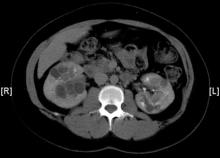

A 43-year-old woman with newly diagnosed hypertension presented to her family physician (FP) with persistent bilateral flank pain. She had a family history of “kidney problems.” Urinalysis, revealed that she had microscopic hematuria. The FP ordered an abdominal computed tomography (CT) scan after a renal ultrasound was suspicious for renal pathology.

The CT scan showed bilateral polycystic kidneys. Polycystic kidney disease (PKD) is a manifestation of a group of inherited disorders resulting in renal cyst development. In the most common form, autosomal-dominant polycystic kidney disease (ADPKD), extensive epithelial-lined cysts develop in the kidney; in some cases, abnormalities also occur in the liver, pancreas, brain, arterial blood vessels, or a combination of these sites.